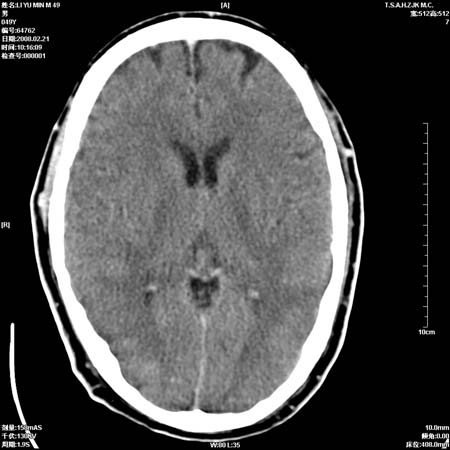

男性, 49岁, 头痛, 行ct检查后, 我科一名大夫报了蛛网膜下腔出血, 请大家讨论!

大脑纵裂池及鞍上池应该有蛛血

支持蛛网膜下腔出血。

支持蛛网膜下腔出血

支持出血